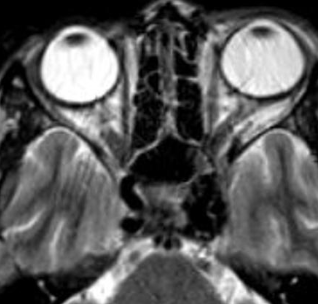

Thrombose de la veine ophtalmique supérieure

- Dans les sinusites ++

- Douleurs orbitaires, proptose, symptomes visuels…

- Elargissement de la veine

- Hyper T1

- Déplacement inférieur du nerf optique